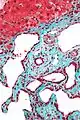

| Histopathology of a bile duct hamartoma, low magnification, H&E stain, showing a well demarcated lesion. |

- Small to medium sized, irregularly shaped bile ducts lined by bland cuboidal epithelium (may also be flattened).

- Prominent intervening collagenous stroma.

- Bile ducts containing eosinophilic debris (may also contain inspissated bile)